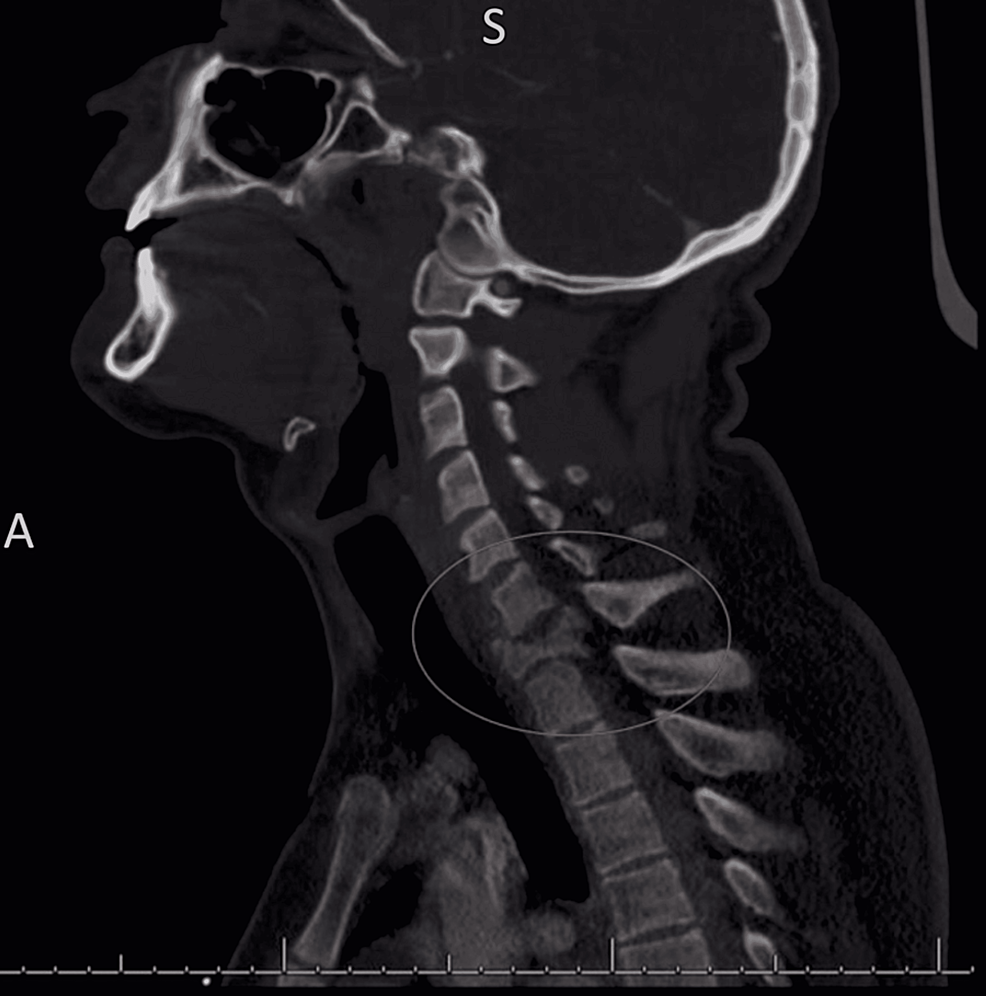

From neuroradiologyteachingfiles.com

bilateral vertebral artery dissection with occlusion Vertebral Artery Occlusion Blood Pressure We currently treat patients with angioplasty and stenting of the extracranial vertebral artery if patients are symptomatic with either a tia or stroke despite maximal medical. Risk of stroke due to symptomatic vertebral artery stenosis can be significantly reduced with implementation of. Background and purpose— few data exist about clinical, radiologic findings, clinical outcome, and its predictors in patients. “rotational. Vertebral Artery Occlusion Blood Pressure.